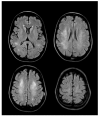

Vitamin B12 deficiency causes a wide range of hematological, gastrointestinal, psychiatric and neurological disorders. Hematological presentation of cobalamin deficiency ranges from the incidental increase of mean corpuscular volume and neutrophil hypersegmentation to symptoms due to severe anemia, such as angor, dyspnea on exertion, fatigue or symptoms related to congestive heart failure, such as ankle edema, orthopnea and nocturia. Neuropsychiatric symptoms may precede hematologic signs and are represented by myelopathy, neuropathy, dementia and, less often, optic nerve atrophy. The spinal cord manifestation, subacute combined degeneration (SCD), is characterized by symmetric dysesthesia, disturbance of position sense and spastic paraparesis or tetraparesis. The most consistent MRI finding is a symmetrical abnormally increased T2 signal intensity confined to posterior or posterior and lateral columns in the cervical and thoracic spinal cord. Isolated peripheral neuropathy is less frequent, but likely overlooked. Vitamin B12 deficiency has been correlated negatively with cognitive functioning in healthy elderly subjects. Symptoms include slow mentation, memory impairment, attention deficits and dementia. Optic neuropathy occurs occasionally in adult patient. It is characterized by symmetric, painless and progressive visual loss. Parenteral replacement therapy should be started soon after the vitamin deficiency has been established.